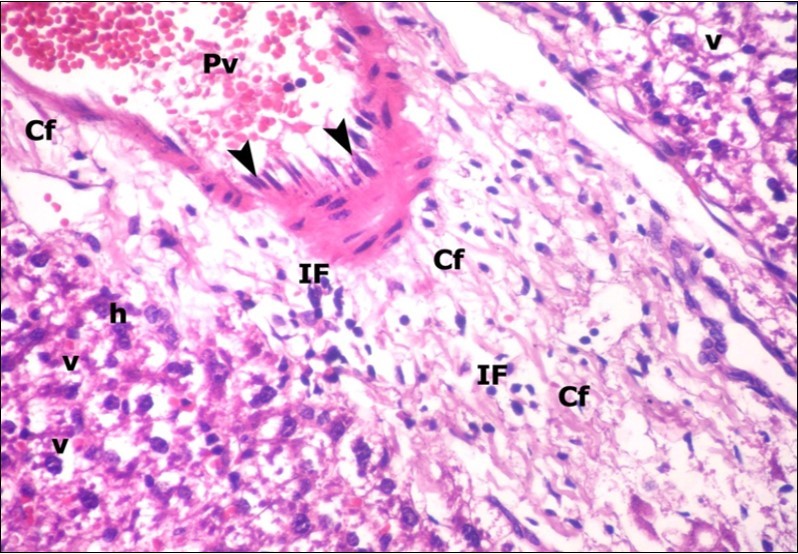

Examination of H&E stained sections of the 1st group (control group) revealed hepatic architecture of tightly packed cords of hepatocyte with vesicular nuclei and acidophilic cytoplasm radiating from the central vein (Figure 1). Portal area was composed of a portal vein, branch of hepatic artery and bile duct lined by single cuboidal cells with dark rounded nuclei. Blood sinusoids with their endothelial lining of Kuppfer cells were noticed in between hepatic cords (Figure 2). Examination of the liver sections of the 2nd group (vitamin E treated group) showed nearly the same histological features as the 1st group. The 3rd group (ZnONPs-treated group) showed a marked loss of the normal liver arrangement with dilated congested central veins and blood sinusoids. Most of hepatocytes had large cytoplasmic vacuoles and darkly stained nuclei other hepatocytes were ballooned (Figure 3). The portal area showed dilated congested portal vein with proliferation of bile duct, necrotic foci in between the hepatocytes with inflammatory cellular infiltration (Figure 4). The portal area showed also elongation of the endothelial lining of dilated congested portal vein and increasing amount of connective tissue fibers (Figure 5). There was congested hepatic artery with increasing thickness of its muscular layer (Figure 6). Bile duct showed proliferation with stratification of its epithelial lining (Figure 7).

Figure 5.A photomicrograph of a section in the liver of ZnONPs-treated adult albino rat showing congested portal vein (Pv) with elongation of its endothelial lining (arrow head) and increasing amount of connective tissue fibers (Cf). Mononuclear cellular infiltration (IF) and hepatocytes with darkly-stained nuclei (h) and vacuolated cytoplasm (v) could be demonstrated. (H&E X400)